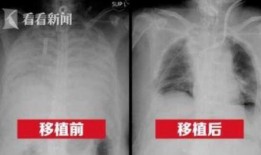

港媒最新爆料新冠肺病人,新冠肺病患者真实生活现状及挑战”

最近港媒可是爆出了一个大新闻,让人不禁瞪大了眼睛!说的是新冠肺病人的一些最新情况,听起来是不是有点刺激?那就跟着我一起,来揭开这...